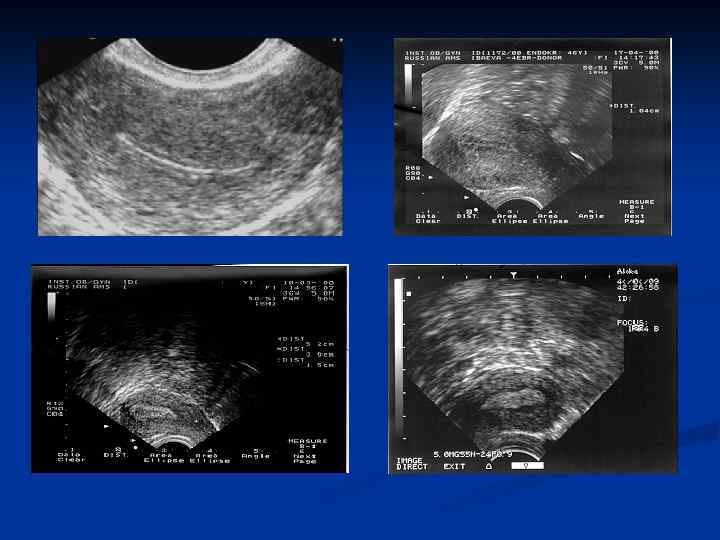

Железистая гиперплазия эндометрия (типичная) n часто определяется у больных с ановуляторными ДМК n при УЗИ – утолщенный неоднородный эндометрий n при выскабливании полости матки –обильный соскоб n при макроскопическом исследовании удаленной матки утолщенный до 1 – 2 см эндометрий n при гистологическом исследовании: повышение количества элементов стромы, желез, с некоторым преобладанием желез. Железы различной формы, могут быть кистовидно расширенные железы, железы выстланы высокопризматическим эпителием, встречаются фигуры митоза n малигнизация встречается в 0, 4 - 1 %

УЗИ. Гиперплазия эндометрия